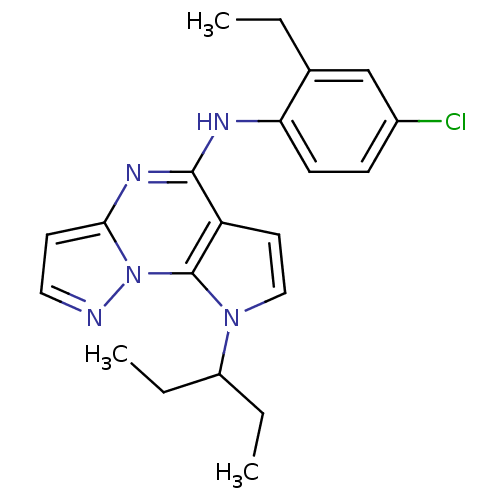

TargetCorticotropin-releasing factor receptor 1(Homo sapiens (Human))

Dupont Pharmaceuticals

Curated by ChEMBL

Dupont Pharmaceuticals

Curated by ChEMBL

Affinity DataEC50: 0.300nMAssay Description:Antagonist activity at human CRF1 receptor expressed in CHO-K1 cells assessed as CRF-stimulated cAMP accumulation by enzyme immunoassayMore data for this Ligand-Target Pair

Affinity DataEC50: 0.420nMAssay Description:Antagonist activity at CRF-R1 in mouse AtT-20 cells assessed as inhibition of human CRF induced cAMP accumulation after 30 mins by radioimmunoassayMore data for this Ligand-Target Pair

Affinity DataEC50: 0.440nMAssay Description:Antagonist activity at CRF-R1 in mouse AtT-20 cells assessed as inhibition of human CRF induced cAMP accumulation after 30 mins by radioimmunoassayMore data for this Ligand-Target Pair

Affinity DataEC50: 0.450nMAssay Description:Antagonist activity at CRF-R1 in mouse AtT-20 cells assessed as inhibition of human CRF induced cAMP accumulation after 30 mins by radioimmunoassayMore data for this Ligand-Target Pair